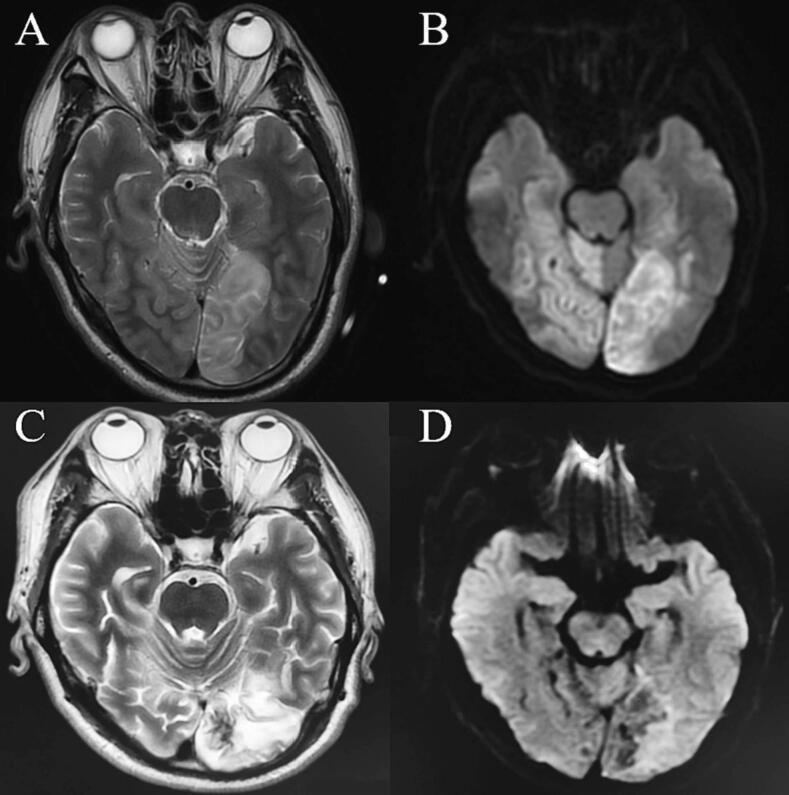

This study reports on a 55-year-old male who showed partial bilateral posterior cerebral artery cortical branch occlusion after timely embolectomy due to thrombus dislodgement during right vertebral artery opening, stenting resulting in basilar artery tip occlusion. The lesions were mainly located in the right cerebellar hemisphere and bilateral occipital lobes, and the patient suffered from bilateral loss of vision, with only light perception preserved. The patient began to receive visual recovery training and 15 sessions of right occipital high-frequency transcranial magnetic stimulation 5 days after the onset.